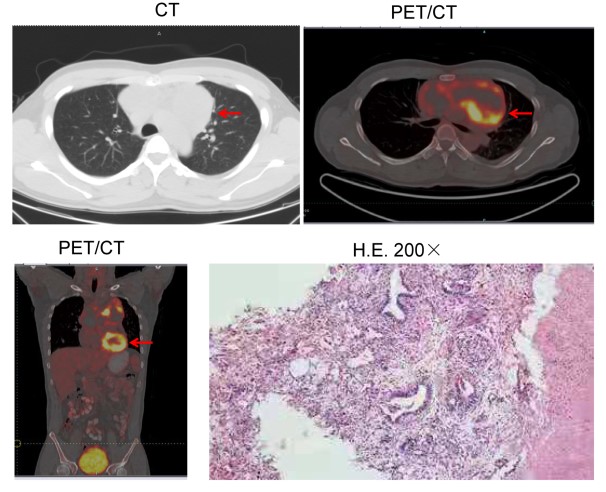

近日,求臻医学与青岛市中心医院放疗科张小涛主任合作,首次报道了一例有BRCA2胚系移码突变(NM_000059.3:exon11: c.4563_4564delAT: L1522fs)的难治性转移性纵隔卵黄囊瘤患者对局部放疗有显著反应。目前该案例报道(case report)已在线发表于Cancer Biology & Therapy(IF:4.742)。 研究背景 卵黄囊瘤,即内胚层窦瘤,是发生在卵黄囊内的高度侵袭性生殖细胞肿瘤。根据位置,可分为性腺卵黄囊瘤和性腺外卵黄囊瘤。性腺外卵黄囊瘤相对少见。它们通常发生在身体的中轴,如大脑、纵隔和腹膜后。纵隔卵黄囊瘤在婴儿期和青春期后更常见。 目前,卵黄囊瘤的标准治疗方案是博莱霉素(Bleomycin)、依托泊苷(Etoposide)和顺铂(Cisplatin)(BEP)化疗后进行手术。然而,由于恶性程度高,诊断时不可能完全切除,原发性纵隔卵黄囊瘤的预后极差,5年生存率为40%-50%,复发后仅仅有6个月的生存期。 过往研究表明,原发性纵隔卵黄囊瘤患者对化疗反应良好,但对放疗反应较差。据报道,某些病例对放射治疗敏感。 然而,目前对原发性纵隔卵黄囊瘤精准放疗的预测性生物标志物尚未被探索。 DNA损伤修复(DDR)对恶性和正常细胞的生存都至关重要。临床前数据显示,辐射敏感性与DDR有关。近期研究表明,DDR基因突变可能预测多种实体瘤患者对放疗敏感性增强。 本案例报告了一例难治性转移性原发性纵隔卵黄囊瘤男性患者。当患者接受化疗,同时使用或不使用特瑞普利单抗(Toripalimab, PD-1抗体)时,疾病进展迅速。然而,该患者对局部放疗很敏感。通过全外显子组测序(WES)在患者体内检测到了BRCA2胚系移码突变。 病例分享 上下滑动查看所有内容 病例讨论 放疗在纵隔卵黄囊瘤的治疗中起着至关重要的作用。为了最大限度地从放疗中获益,探索与疗效相关的生物标志物至关重要。以往的研究证明,包括BRCA1/2在内的DDR基因突变可能会增强多种实体瘤患者的放射敏感性。然而,DDR基因突变作为原发性纵隔卵黄囊瘤放疗的预测性生物标志物尚未被探索。 放射敏感性取决于多种因素,例如肿瘤组织学、辐射剂量和肿瘤细胞的固有放射敏感性等。其中肿瘤细胞的内在放射敏感性是最重要的因素。由于放疗主要通过产生DNA双链断裂(DSB)诱导细胞死亡,DDR无疑会影响肿瘤细胞的放射敏感性。 DDR系统通过八条途径修复多种形式的DNA损伤,以适当保护基因组的完整性。这八条途径包括错配修复(MMR)、碱基切除修复(BER)、核苷酸切除修复(NER)、同源重组修复(HRR)、非同源末端连接(NHEJ)、检查点因子(CPA)、范科尼贫血(FA)和易位DNA合成(TLS)。其中HRR和NHEJ通路负责修复DSB, BER负责修复单链断裂(SSB),MMR通路负责修复DNA插入/缺失。 BRCA1和BRCA2是介导HRR途径的两个关键分子。这两个基因的突变可能会破坏DSB的修复。由于辐射主要通过产生DNA双链断裂诱导细胞死亡, BRCA1或BRCA2突变的恶性肿瘤通常会导致HRR通路的缺陷,因此对电离辐射反应良好。 目前纵隔卵黄囊瘤的标准治疗方案是新辅助化疗后将残余肿块切除术。由于确诊时肿瘤通常巨大且常与邻近器官有纤维粘连,化疗后残余肿瘤的完全切除非常困难,也间接导致了本病较差的预后。新辅助化疗是纵隔卵黄囊瘤的主要治疗方法,初始治疗方案推荐以铂为基础的化疗,常用方案为4-6个周期的VIP(顺铂、依托泊苷和异环磷酰胺)或BEP。含铂方案化疗使高达50%的患者实现了长期生存。我们检索到了许多新辅助化疗后R0切除及术后达到病理学完全缓解(PCR)的报道。对于化疗和手术后复发的纵隔卵黄囊瘤患者,再次化疗的效果很差。本例患者对化疗不敏感,原因尚不明确。 此外,患者对免疫检查点抑制剂(ICI)治疗不耐受。可能与患者MSI-L、TNB-L和HLA LOH强阳性有关(表1)。HLA LOH强阳性意味着HLA-A、B和C三个基因同时缺失。HLA LOH是免疫逃逸的常见原因。这是由于抗原提呈细胞通过HLA I类分子的抗原提呈新抗原在细胞免疫中起着关键作用。HLA-LOH导致抗原呈递减少,从而促进了免疫逃逸。 此前的研究表明,BRCA1突变的携带者患乳腺癌、卵巢癌、前列腺癌和结肠癌的风险增加,而BRCA2突变的携带者患男性乳腺癌、胰腺癌和前列腺癌的风险更高。目前卵黄囊瘤的发病机制尚不清楚。然而,该患者的BRCA2胚系移码突变应该与其病因密切相关。BRCA2胚系突变导致负责DSB修复的HRR通路缺陷。 PARP抑制剂可能抑制PARP-1介导的SSB修复(即BER通路),从而增加DNA链断裂的积累,促进基因组不稳定性和细胞凋亡。根据合成致死率的概念,PARP抑制剂可以有效地摧毁BRCA基因缺陷的肿瘤以及同源重组能力较低的睾丸肿瘤细胞系。迄今为止,FDA已批准奥拉帕利用于治疗BRCA胚系突变的卵巢癌、乳腺癌和前列腺癌。此外,奥拉帕利在治疗BRCA胚系突变的胰腺癌和小细胞肺癌(SCLC)方面也表现出显著的临床疗效。 此外,Yue Bi等人的一项研究表明,奥拉帕利作为一种有效的放射增敏剂,在BRCA1缺陷型高级别浆液性卵巢癌的临床前模型中具有潜在的应用价值。这使我们联想到PARP抑制剂可能被用作潜在的放射增敏剂,以提高BRCA2突变患者的放疗敏感性。正如所料,本案例中的患者对局部放疗联合奥拉帕利治疗表现出良好的反应。 结论与启发 该病例报告首次描述了一例BRCA2胚系移码突变的难治性转移性纵隔卵黄囊瘤患者对放疗具有显著反应,可为临床实践中的精确放疗提供有见地的线索。